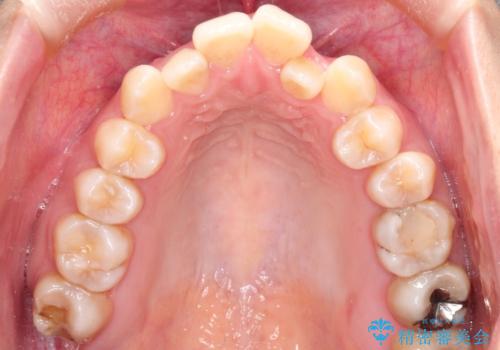

- 前歯のガタガタと、かみ合わせを改善したいとのことで来院されました。

下顎の歯が、上顎の歯に対して前方に位置していたので、下顎の歯を後方に移動させるのと、歯と歯の間を削りスペースを作り、歯を並べる計画としました。